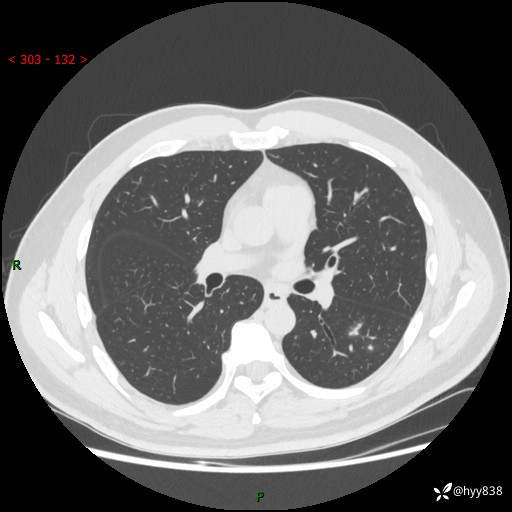

中年男性,胸闷3月余。多发团片、肺小叶分布、空气支气管征、明显强化---结果公布~

现病史:患者3月前出现胸闷,卧位时加重,坐位时缓解,无咽痛、咳嗽,无头痛,无全身酸痛,无结膜充血,无胸痛、心慌,无咯血,无呼吸困难,无咳痰,2024-07-02于当地市第一民医院行胸部CT,结果不详,2024-07-05就诊于我院急诊内科,行胸部CT同时增强,结果示:左肺下叶多发结节灶,考虑感染可能。今患者为求进一步诊治来我院,门诊以“肺部感染”收入我科。 患者本次起病来精神、食欲、睡眠尚可,大小便可,体力,体重无明显变化。

胸部CT平扫+增强

各期CT值:30hu 90hu 77hu